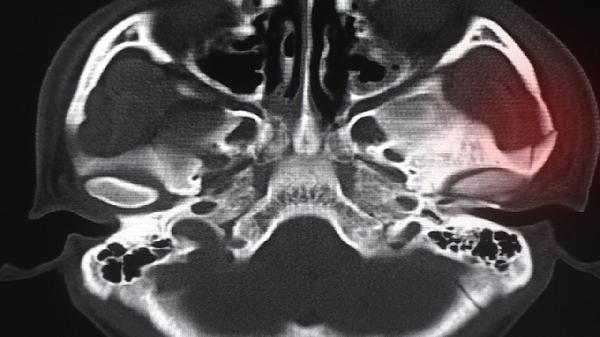

骨质硬化有什么危害

骨质硬化是一种骨骼疾病,会导致骨骼密度异常增加,影响骨骼的正常功能,可能引发骨折、疼痛和关节活动受限等问题。预防和治疗骨质硬化需要从生活方式、饮食和医学干预多方面入手。